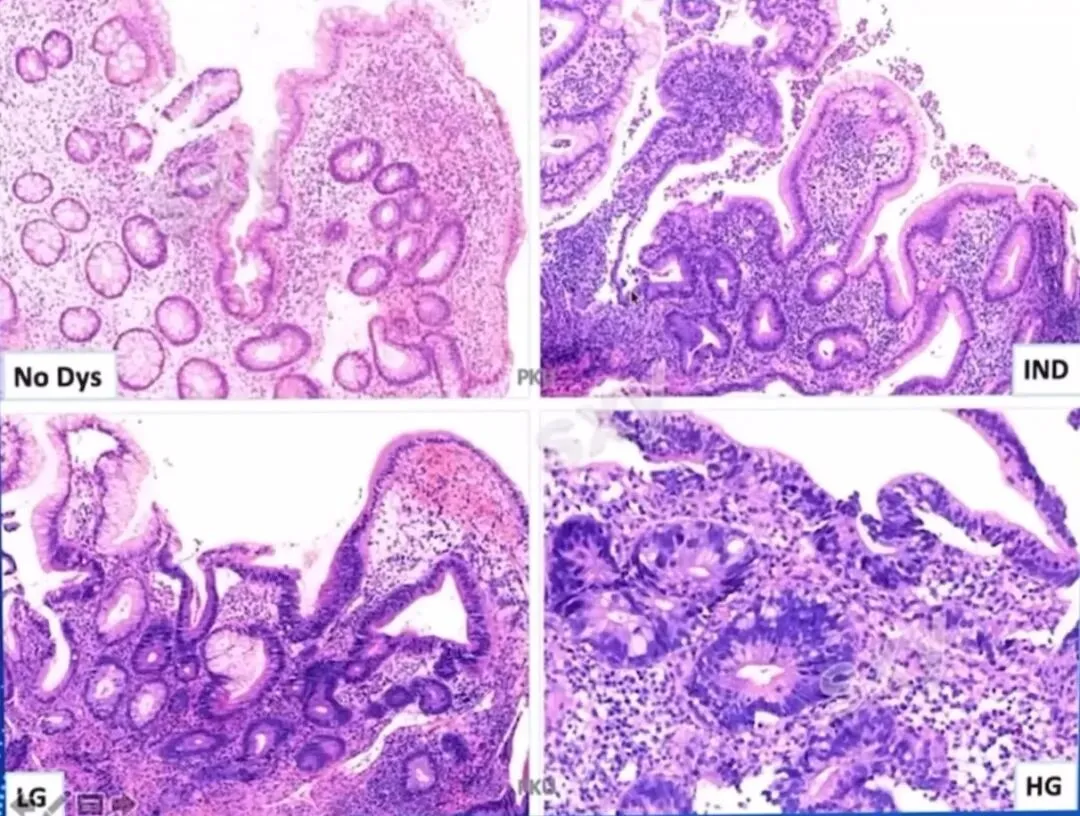

>课件分享:炎症性肠病的病理诊断

课件分享:炎症性肠病的病理诊断